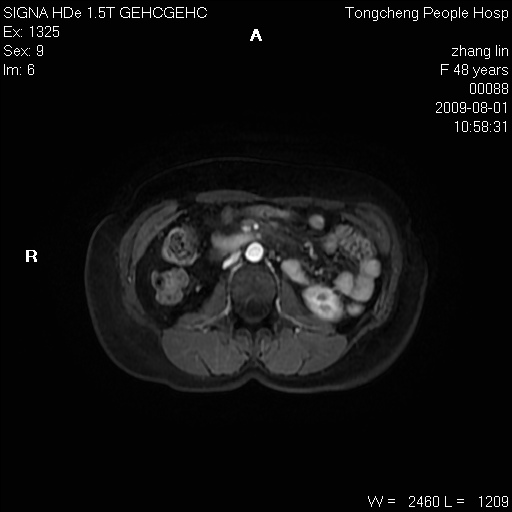

女,48岁。健康体检,彩超发现右肾占位性病变。平素健康。

临床诊断:右肾占位性病变,性质待定(囊肿?肿瘤?)。

上中腹部mr平扫+增强扫描,图像如下:

右肾上极见一类圆形病灶,t1wi呈等信号t2wi呈等高混杂信号,三期增强无强化,边界清---考虑囊肿出血。

同反相位均表现为等信号,病变无强化,考虑含蛋白的囊肿可能,弥散加权相或许有些帮助,

慢性胆囊炎